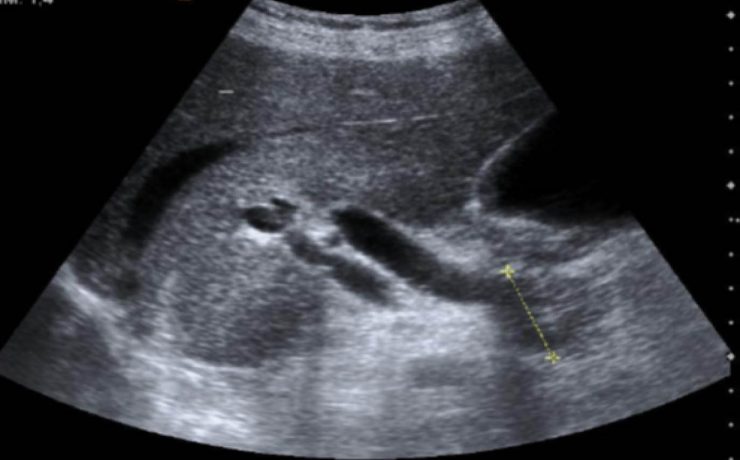

El bazo es el órgano más frecuentemente lesionado tras un traumatismo abdominal cerrado con una incidencia que se reporta entre 32 y 45%. El abordaje diagnóstico y terapéutico de estos pacientes ha evolucionado notablemente en las últimas décadas desde la exploración física hacia la exploración tomográfica para el diagnóstico y